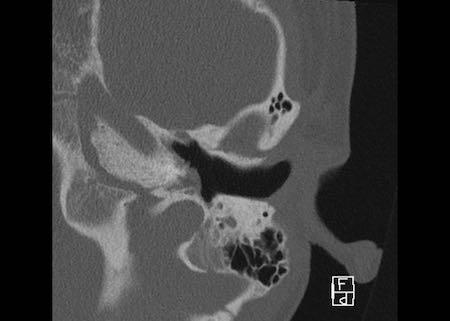

Bé trai 8 tuổi được cấy ghép ốc tai hai bên. Vị trí bình thường ở tai phải.

Một điện cực được đặt đúng vị trí với tất cả các kênh của nó, hiện ra như một chuỗi hạt, nằm trong ốc tai và xoắn lên theo hướng đỉnh ốc tai.

Tiếp tục xem hình ảnh của tai trái.